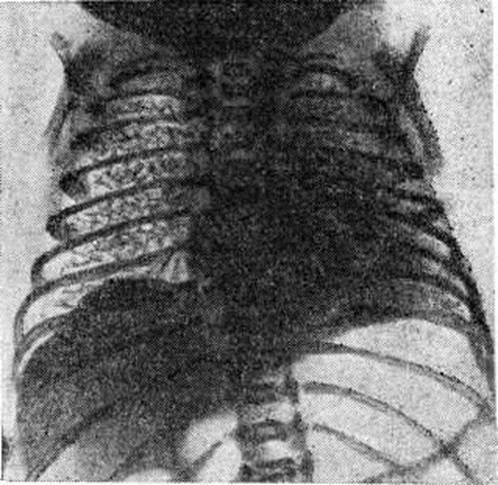

Рисунок 2.

Рентгенограмма грудной клетки ребёнка 15 часов жизни, страдающего гиалиново-мембранной болезнью: на всем протяжении правого лёгкого видна характерная сетчатость лёгочного рисунка, ателектазы в левом лёгком.

Основной методикой исследования является рентгенография грудной клетки. Рентгенологическое признаками Гиалиново-мембранная болезнь новорожденных на рентгенограмме лёгких (рисунок 2) являются: 1) характерная патологическая сетчатость лёгочного рисунка; иногда наблюдаются беспорядочно расположенные участки уплотнения лёгочной ткани (ателектазы), чередующиеся с участками просветления за счёт локального вздутия лёгких; 2) наличие светлых полосок бронхиальных разветвлений, различимых на фоне малопрозрачного лёгкого; 3) в тяжёлых случаях имеется диффузное понижение прозрачности лёгочных полей (так называемый белое лёгкое). Отмечается необычная форма грудной клетки — с опущенными рёбрами. Иногда на рентгенограмме могут наблюдаться пневмоторакс (смотри), интерстициальная и медиастинальная эмфизема (смотри), возникающие в связи с разрывом бронхиол.